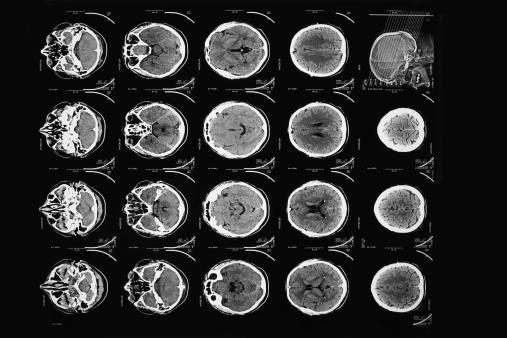

Modern CT scans provide much higher resolution images of the 'slices' of the brain than Hounsfield's original scan did in 1971.